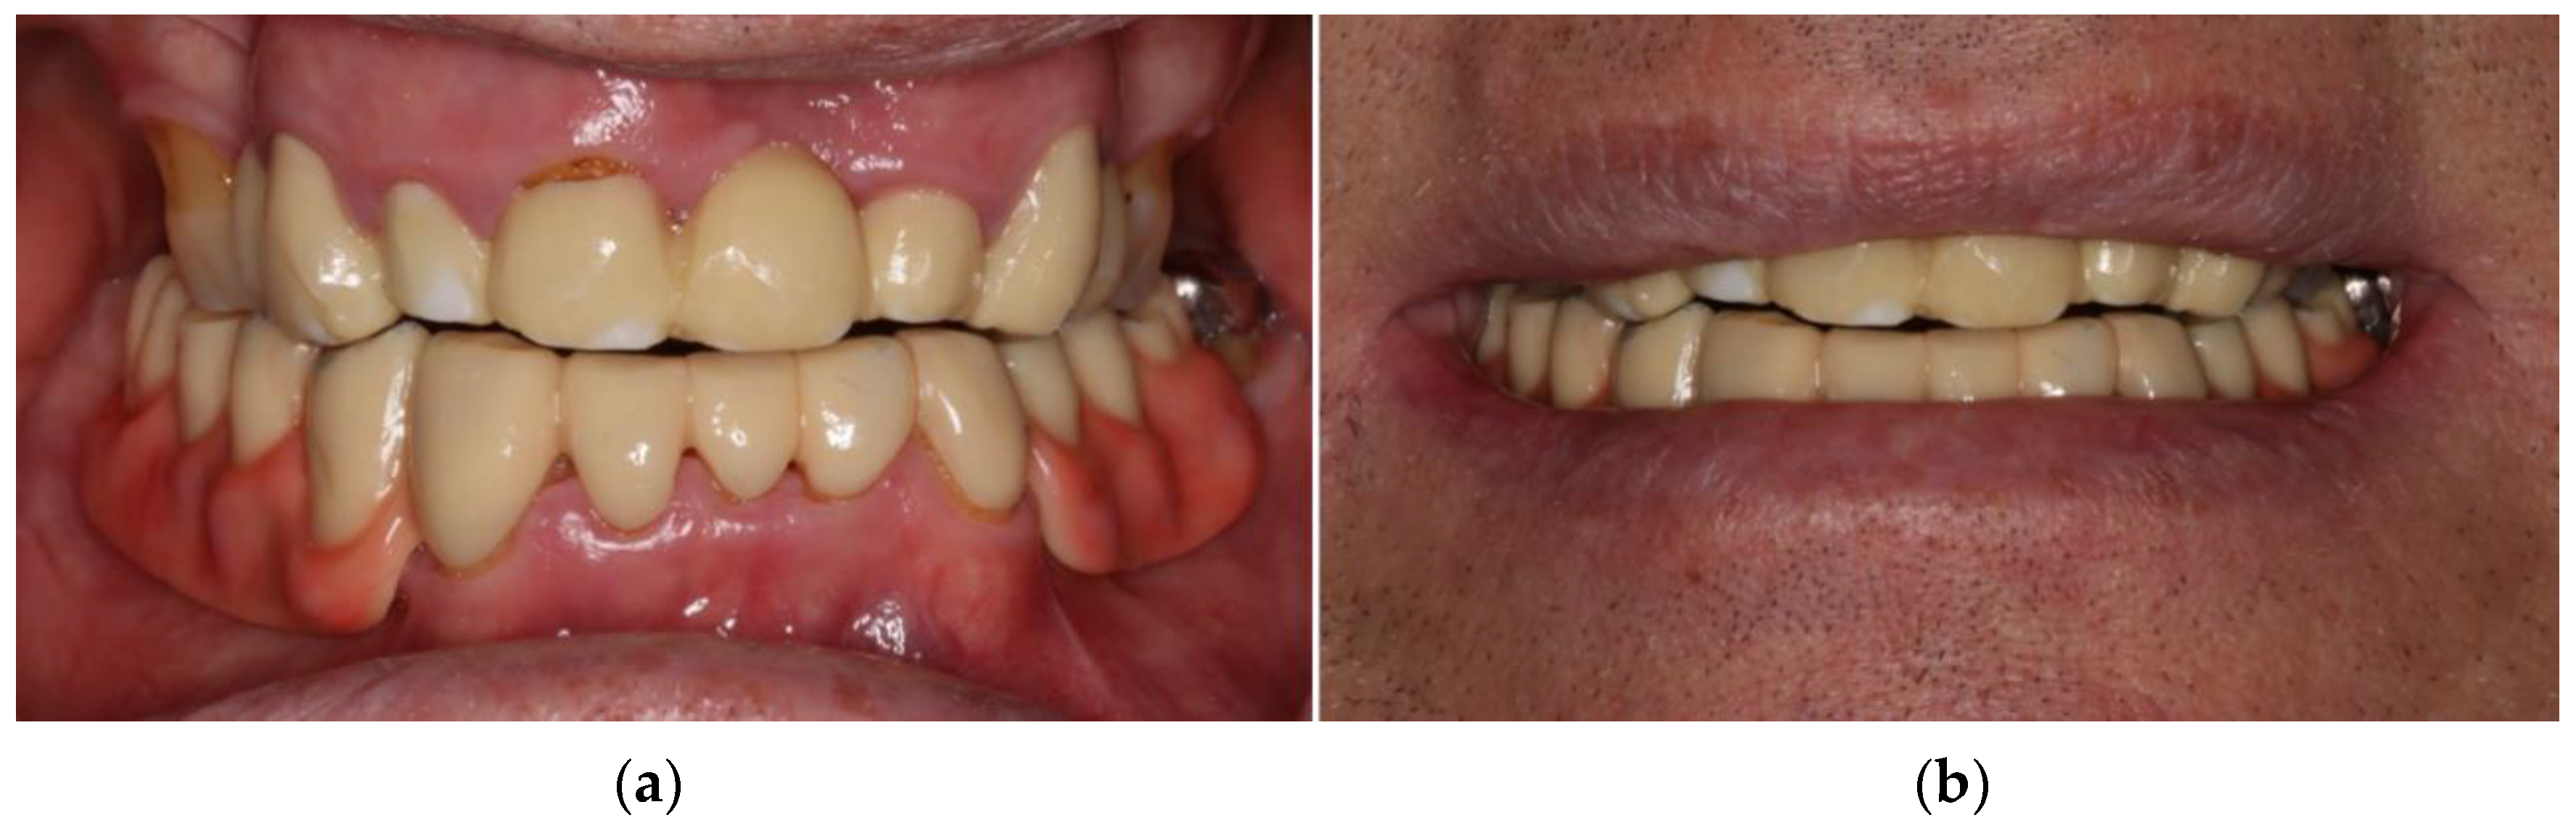

- Locator abutments on both implants, single-crown FDPs on the remaining lower molar teeth, insertion of a tooth-colored and tooth-shaped monolithic RDP fabricated from POM with minimally invasive preparation of the lower anterior teeth (experimental character in long-term endurance).